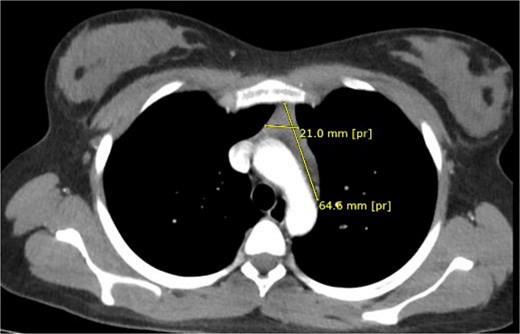

High-resolution chest computed tomography (CT) demonstrated a homogeneous anterior mediastinal mass measuring 61 × 24 mm, consistent with thymic hyperplasia (Fig. 1).

Preoperative thoracic CT showing a 61 × 24 mm homogeneous anterior mediastinal mass.